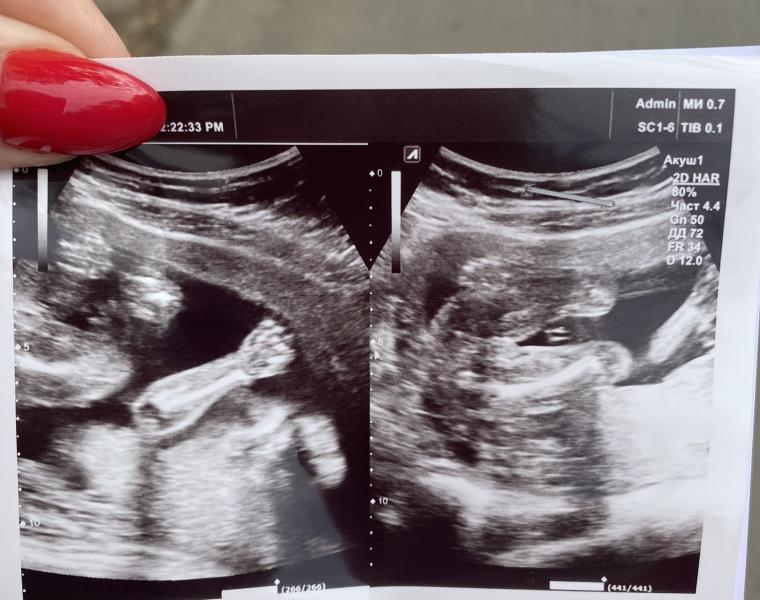

На этот раз мне уже дали фото🤣слева ручка нашей малышки, а справа уже вот прям , что девочка девочка😍